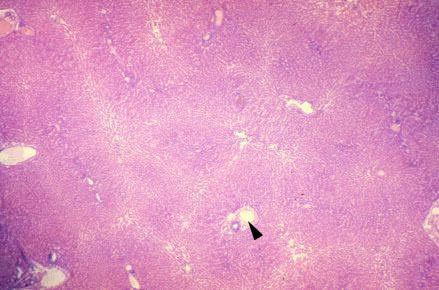

VIII-25, Slide 64, Liver (H&E). This is a low power view of the liver showing lobules and portal triads (arrowhead).